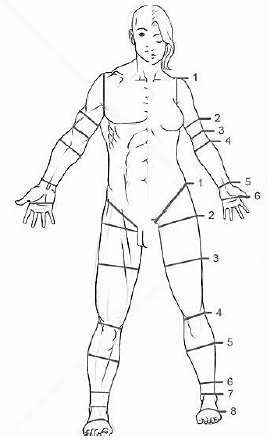

A imagem abaixo mostra o nível de algumas amputações e desarticulações, assinale a alternativa correta: